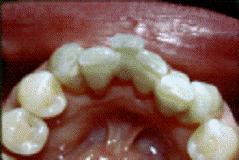

Интракоронковое шинирование. Этот

вид шинирования используется во фронтальной и жевательной группе зубов.

Шина покрывается композитным

материалом в тон зуба.

Для интракоронкого шинирования

применяется арматура на основе не органической матрицы. Стекловолокна имеют

лучшую биосовместимость с тканями человеческого организма, так как состоят из

биоинертного стекла, а не из пластика. Она (арматура на основе не органической

матрицы) не требует специальных условий хранения, легко режется обычными

ножницами, хорошо адаптируется ко всем поверхностям зубного ряда. Выпускают ее

модификацию в виде полого жгутика, что значительно расширяет сферу применения.

Жгутик оптимален для шинирования жевательной группы зубов с использованием

техники создания бороздки, для восстановления одиночного дефекта зубного ряда

или в качестве альтернативы внутрикорневым штифтам.